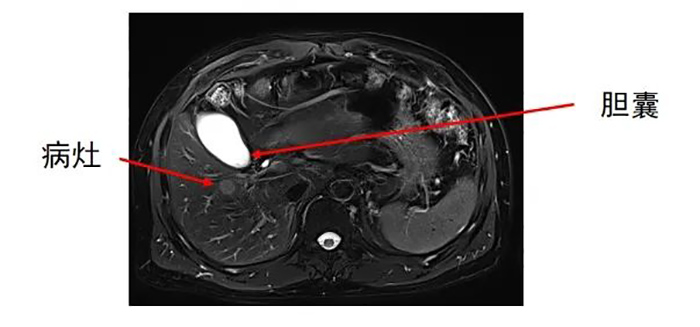

肝内转移灶数目为两个,分别位于左叶和右叶。

齐先生病灶临近大血管、重要脏器。厦门三院专家团队在CT引导下精准定位,经皮穿刺将微波消融针准确置入齐先生肝脏肿瘤部位,然后利用微波能量,使肿瘤组织内的水分子快速振动、摩擦产生热量,从而使局部温度迅速升高,让肿瘤细胞凝固性坏死。整个手术过程顺利,避免了严重并发症发生。

准确插入到病灶内,并避开了门静脉右支及胆,避免了出血、损伤胆囊等并发症。